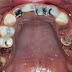

Nhiều người lầm tưởng vôi răng là men răng nên khi nhắc đến việc cạo vôi răng, họ thường lo sợ sẽ làm mòn men răng, gây yếu răng,…Tuy nhiên, việc cạo vôi răng thực chất chỉ là thao tác giúp vệ sinh răng miệng, loại bỏ mảng bám, vi khuẩn lâu ngày không được thực hiện.

Việc cạo vôi răng khi nào, bao lâu 1 lần tùy thuộc vào tình trạng răng miệng. Nếu người bệnh có thể quan sát thấy vôi răng bám trên cổ răng, hay chảy máu chân răng thì rất có thể vôi răng đã hình thành. Thông thường, 3-6 tháng người bệnh nên đi thăm khám và cạo vôi răng định kỳ. Với những người mắc bệnh viêm nha chu, viêm chân răng thì cần phải cạo vôi răng thường xuyên. Tuy nhiên, với những người chăm sóc răng miệng tốt, chải răng đúng cách thì vôi răng sẽ ít hình thành hơn, không cần thiết phải cạo quá nhiều lần.

Hiện nay, với kỹ thuật cạo vôi răng bằng máy siêu âm giúp loại bỏ mảng bám trên và dưới nướu tối đa. Dưới tác động của mũi siêu âm với tần số biến điệu cao, vôi bám chạt vào thân răng sẽ được lấy đi sạch sẽ, không gây đau nhức, ê buốt hay chảy máu.

Sau khi lấy vôi răng, bác sĩ sẽ áp dụng kỹ thuật đánh bóng hiện đại sẽ giúp hạn chế khả năng tái bám của các mảnh vụn thức ăn và các hợp chất vô cơ, mang lại cho bạn hàm răng đẹp và khỏe mạnh.